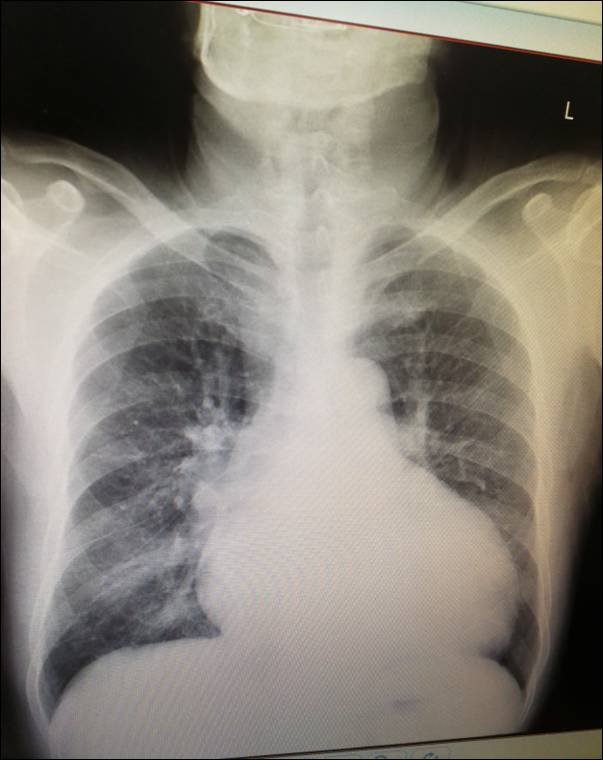

◆入院时间: 2017年4月6日

◆患者近一周来再次出现胸闷、气喘,遂再次入。

◆入院查体:T36.5℃, P 80次/分,R 20次/分,BP 100/75mmHg。口唇无紫绀、呼吸运动正常,双肺底未可闻及湿啰音。心率80次/分,节律不齐,可闻及早搏,二尖瓣听诊区可闻及4/6 级收缩期杂音。双下肢无浮肿。

◆生化:ALb39.9g/L↓、ALT 16U/L、AST 16U/L、总胆红素 19.9umol/l、肌酐 66μmol/L↑、钾 3.52mmol/l 、钠 137mmol/l、氯 97mmol/l、钙 2.47mmol/l、GLU、10.67mmol/l 、NT-ProBNP 4190ng/L↑

◆1、左室壁运动弥漫性减弱 左心及右房大 ,EF 21%,左室缩末内径 76mm,舒末内径85mm。